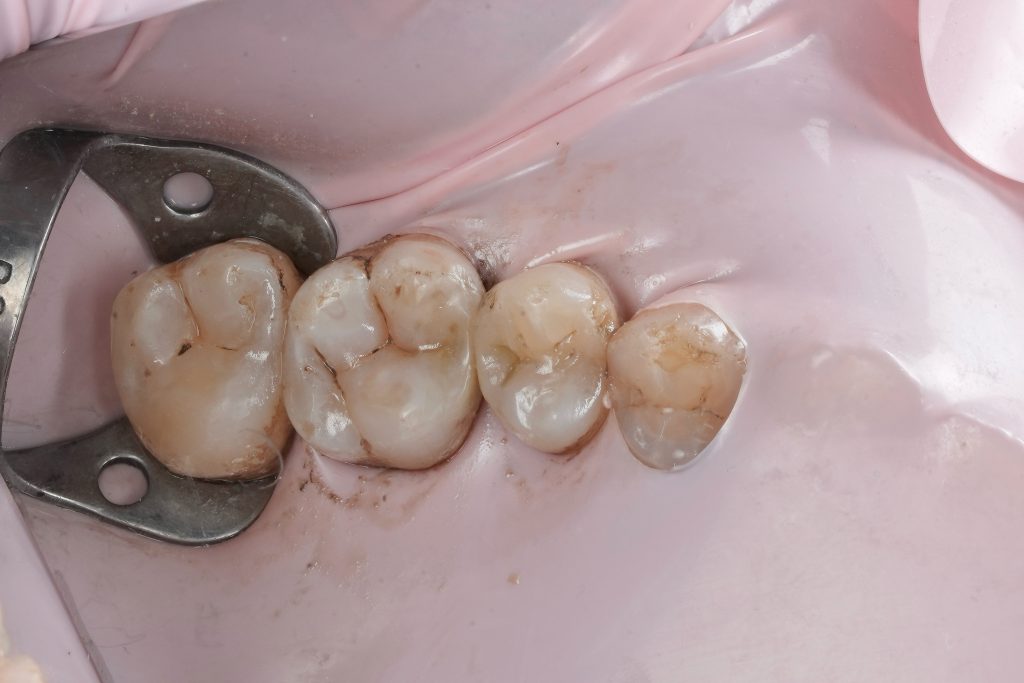

Isolation

Absolute rubber dam isolation was established prior to operative procedures. This ensured:

- A dry, contamination-free field

- Accurate shade perception

- Improved adhesive performance

- Enhanced visibility of cavity margins

Isolation was maintained throughout the procedure without compromise.